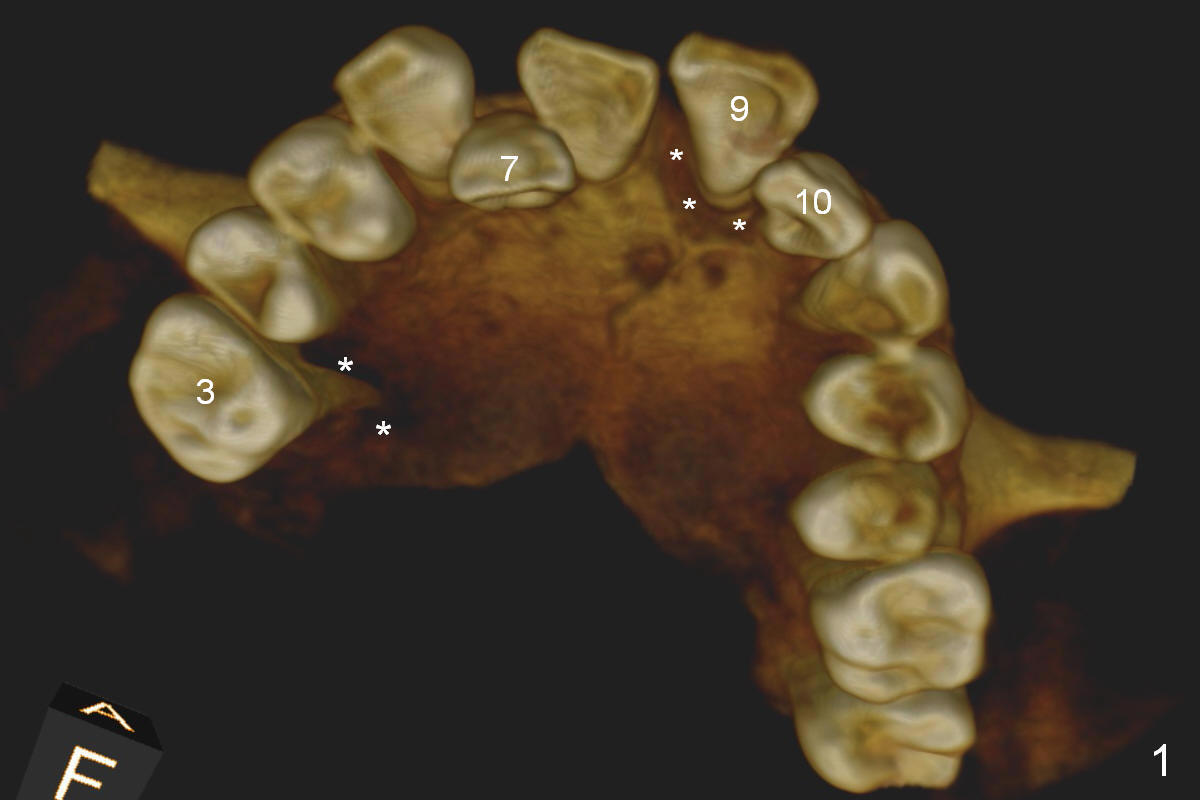

A 45-year-old man (SH) has periodontal (#3,9,19,23 (bone loss: Fig.1-3 *)) and orthodontic (#7,10 cross bite) problems, which he wants to solve at the same times. The tooth #19 is symptomatic (Fig.4,5). Infiltrate the buccal plate with 2% Xylocaine 1:50,000 Epinephrine and Septocaine (away from the Mental Foramen). After extraction and debridement, the socket is treated with Metronidazole. Osteotomy is initiated slightly buccal (B) to the middle of the socket bottom (Fig.5), using Sinus Master Kit drills (6 mm deep). After each drill, gently explore the lingual wall of the osteotomy with a fine curette or an explorer to determine whether the wall is perforated or not. Place a 5.5x13 mm implant (or short) between the buccal plate and the Inferior Alveolar Nerve (brown circle). If the torque is high, use the corresponding drill and tap. A 5.5 mm angled abutment will be used (15 or 25°, will arrive Monday morning). When X-ray is taken, the apex of the osteotomy should be superior to the upper border of the Inferior Alveolar Canal (Fig.4 U) and inferior to the Lower one (L). Bone graft is placed (Fig.4,5 red circles) after placement of PRF buccally (Fig.5 yellow curved line). If visibility is poor, make an incision and insert Epinephrine gauze under periosteum for hemostasis. Take photos when a 2 mm pilot drill in place to show the coronal end of the drill at the lingual cusp instead of the central fossa.